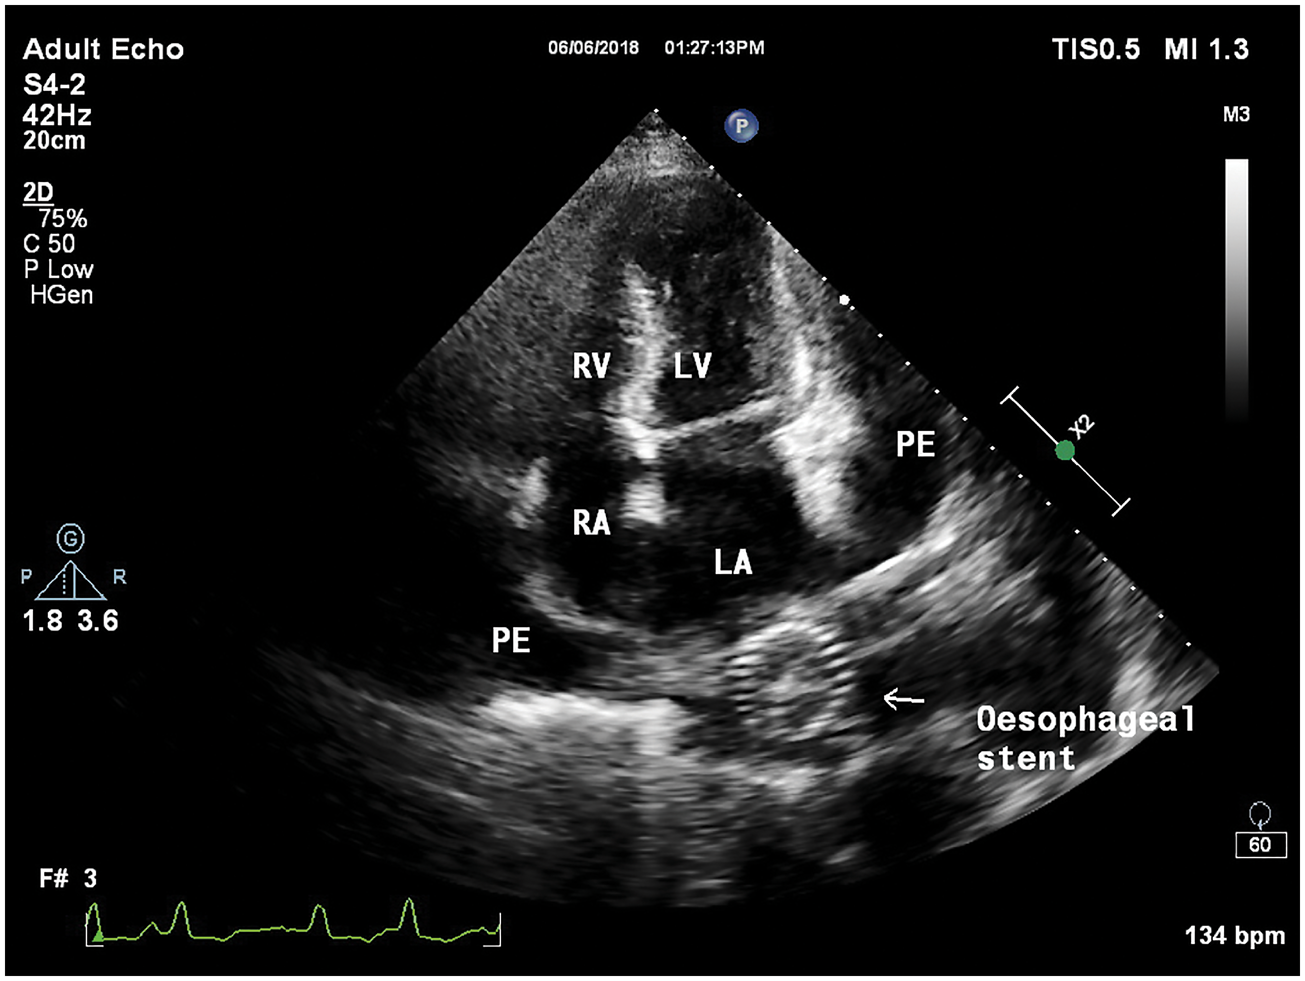

经胸超声心动图检查显示,左心房后有金属阴影,即食管支架(图2,图3)